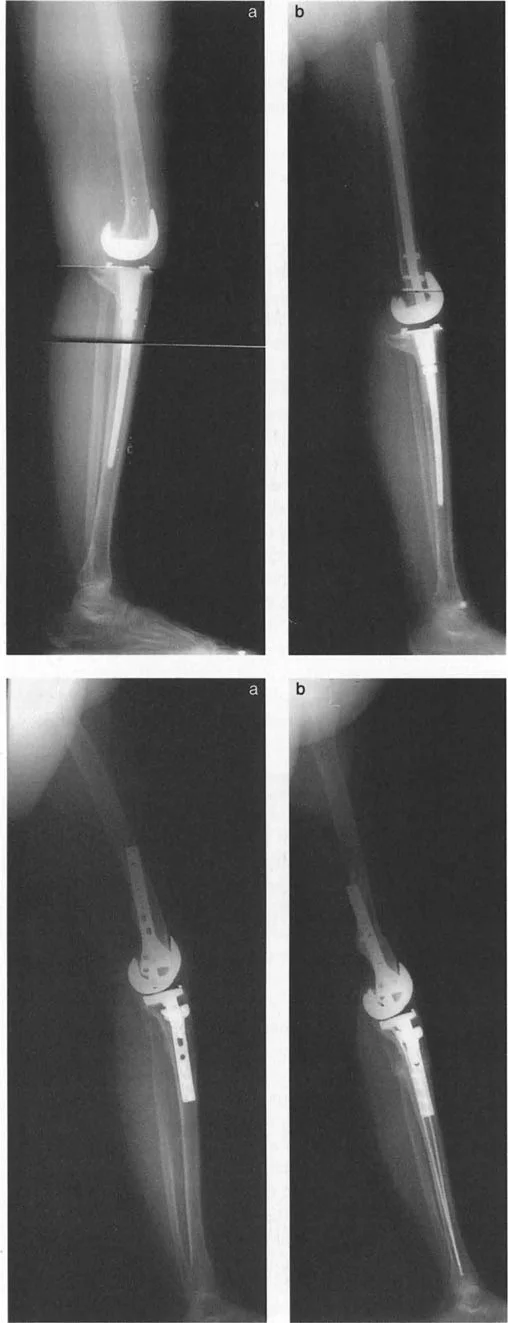

- جراحات قطع العظم وتقويم المحاور

- استبدال المفاصل في حالات التشوه الشديد

في حين أن التشوهات الديناميكية تُناقش غالبًا في سياق أمراض الأعصاب والعضلات لدى الأطفال، فإن المبادئ البيوميكانيكية التي تحكمها تنطبق عالميًا على إعادة بناء العظام لدى البالغين. يشمل ذلك سيناريوهات إعادة البناء المعقدة للغاية، مثل استبدال مفصل الركبة الكلي (TKR) واستبدال مفصل الورك الكلي (THR) المرتبطة بالانحرافات الشديدة خارج المفصل. إن فهم الأذرع الرافعة هو المتطلب الأساسي لإتقان هذه التقنيات المتقدمة في جراحة المفاصل وقطع العظم، وهو ما يتقنه الأستاذ الدكتور محمد هطيف في ممارسته اليومية.